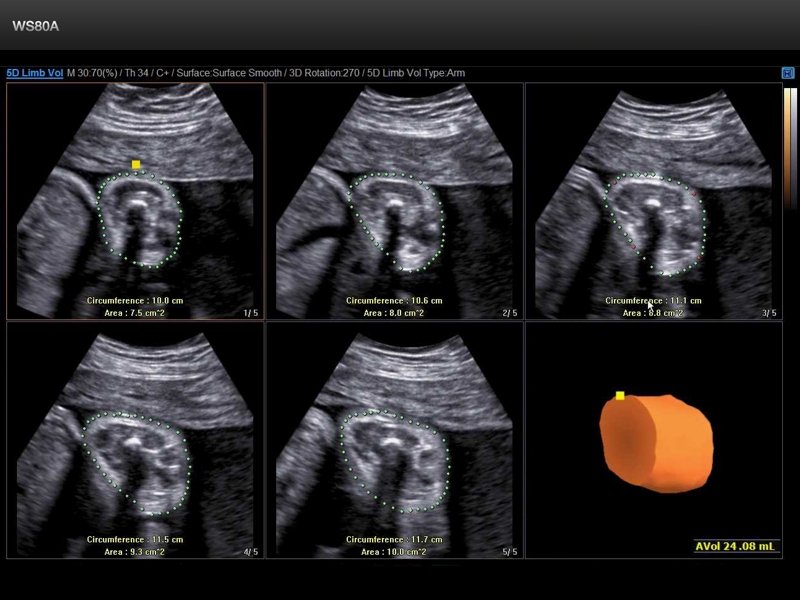

Fetus, 5D Limb Vol (echogramm №660)

[RU] Ultrasound image №660: Fetal weight estimation in 5D Limb Vol mode.

Echogramm was received by ultrasound scanner WS80 (out of production).